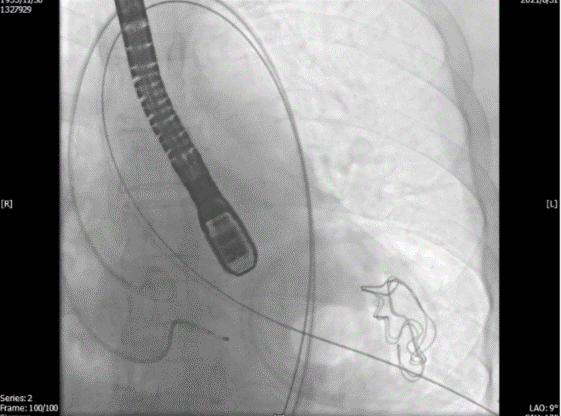

通过TEE确定三个定位件准确入窦后完全释放瓣膜(图4),再次用TEE观察人工瓣膜自膨后金属支架的形态(自膨胀后最大外径)、位置(瓣环下金属支架长度及占比)、有无明显瓣周漏。撤出输送器(图5),收紧心尖处荷包线并打结,检查无出血,逐层关胸,封皮,拔出股动脉鞘并在股动脉穿刺处压迫止血。手术过程顺利,患者生命体征平稳。

图4. TEE和放射线显示人工瓣膜自膨

图5. 放射线显示锁丝松开后,输送器逐步回撤,TEE提示人工瓣(导丝处)微量中心性反流信号